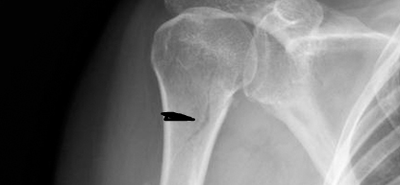

Результат - неполный перелом. Месяц в гипсе. Снимок выглядел как-то так.

Если посмотреть на 2 снимок то увидите облачко вокруг концов отломков!это зарождается первичная мозоль ,которая выходит из гематомы(кровяного сгустка) как Венера из океана)